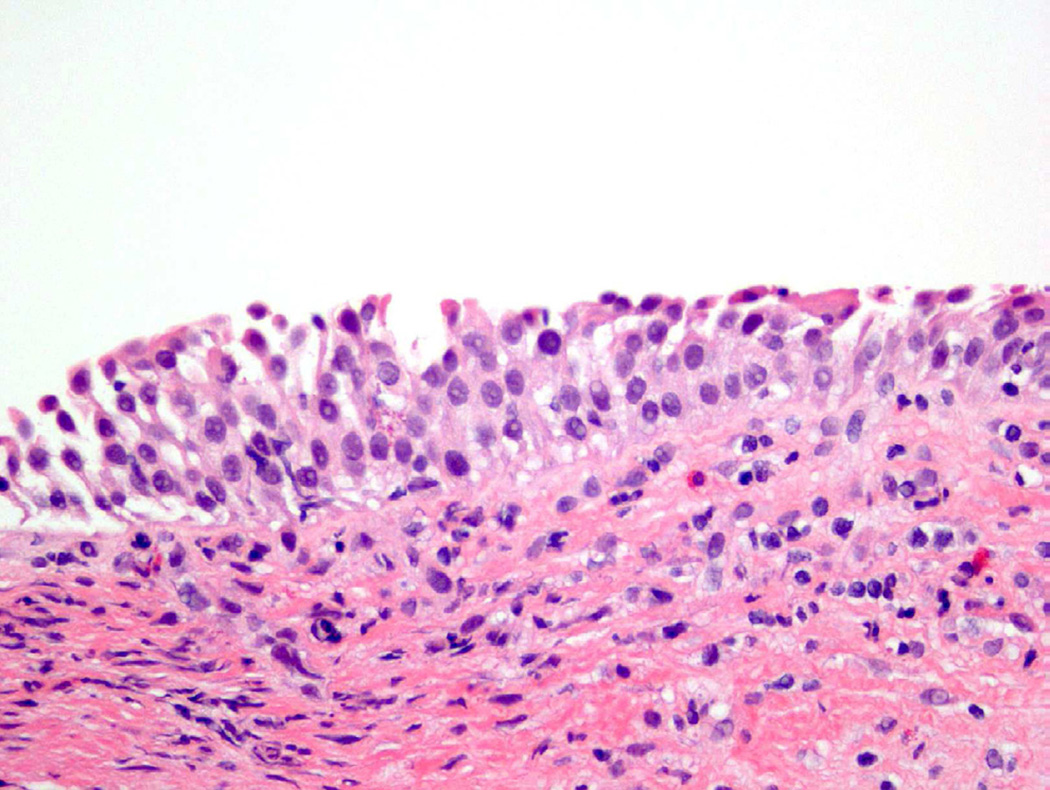

Despite the variety of appearances of a normal urothelial cell, certain specific cellular features are evaluated when determining the presence of atypia. Abnormal nuclear features, including increased size (nucleomegaly), deviation from typical ovoid shape, coarse chromatin, and irregular nuclear membrane contour, are all contributory factors in classifying a cell as atypical (Fig. 2)4. In addition, the identification of an enlarged, prominent nucleolus or multiple nucleoli should raise concern1. While eosinophilic (pink appearing) cytoplasmic features are acceptable in the superficial urothelium, these cytoplasmic changes in other layers, as well as loss of cytoplasmic clearing, are also considered atypical features4.

Figure 2.

Atypia demonstrates subtle changes from normal, which may include occasional hyperchromasia, disorganization, or increased nuclear/cellular variability.